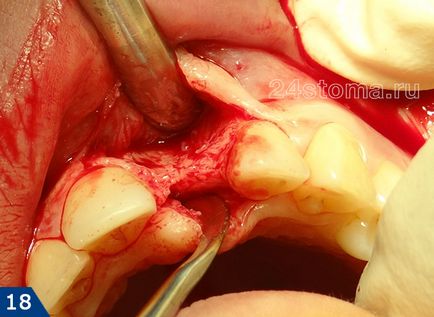

3) tok -

hiányában középső metszőfog felső állkapocsban. Végzett kétlépéses implantációs technika, bonyolult hátránya mértékű csont területén a hiányzó fog. Vezetett kapacitás csont alkalmazásával csontanyag és biológiailag felszívódó membrán.